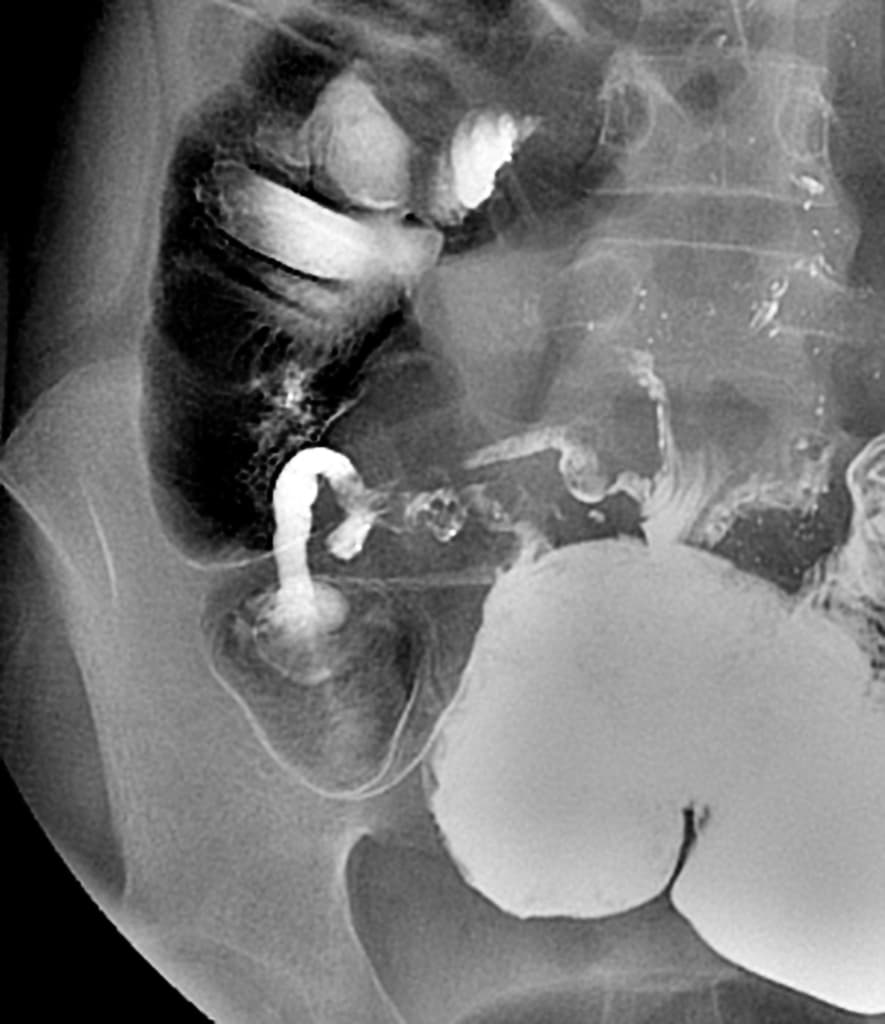

Đau vùng chậu kèm cảm giác khó chịu. Các khối dạng nang vùng chậu trên siêu âm.

Nhiều tổn thương phần phụ dạng nang-đặc hai bên vùng chậu với bờ không đều và tín hiệu hỗn hợp tăng trên T2/giảm trên T1; phần đặc ngoại vi tăng quang sau tiêm. Tổn thương lớn nhất: 65x41 mm (phải), 39x36 mm (trái). Ống dẫn trứng giãn ngoằn ngoèo chứa thành phần hoại tử (21 mm phải, 20 mm trái). Thay đổi dạng nốt viêm và dính trong khoang chậu; mất một phần đường bờ tử cung. Dày dạng nốt nhỏ lan tỏa của mạc nối lớn tạo hình ảnh bánh mạc nối giả. Tổn thương phần phụ trái xâm lấn quai hồi tràng lân cận, biểu hiện giảm tín hiệu T2, hạn chế khuếch tán và tăng quang mạnh; dày đến 11mm, kéo dài khoảng 15cm. Các quai hồi tràng dính nhau nhưng không giãn hay tắc mạch. Tử cung hai sừng hoặc có vách ngăn bán phần. Cơ tử cung, nội mạc tử cung, cổ tử cung và buồng trứng bình thường.

Lao vùng chậu - phúc mạc

- "Lao vùng chậu có thể mô phỏng bệnh lý ác tính buồng trứng trên hình ảnh do các khối dạng nang-đặc và dày mạc nối."

- "Ống dẫn trứng giãn với thành phần hoại tử (viêm ống dẫn trứng) là những chỉ số gợi ý mạnh mẽ về lao."

- "Bánh mạc nối giả và dày mạc nối dạng nốt nhỏ là những đặc điểm đặc trưng của tổn thương phúc mạc."